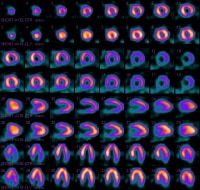

Exercise stress testing, which is now widely available at a relatively low cost, is currently used most frequently to estimate prognosis and determine functional capacity, to assess the probability and extent of coronary disease, and to assess the effects of therapy. Ancillary techniques, such as metabolic gas analysis, radionuclide imaging (see the images below), and echocardiography, can provide further information that may be needed in selected patients, such as those with moderate or prior risk.

MI (see the images below) is a common first presentation of ischemic heart disease. This subset of patients also may require prognostic or risk assessment.